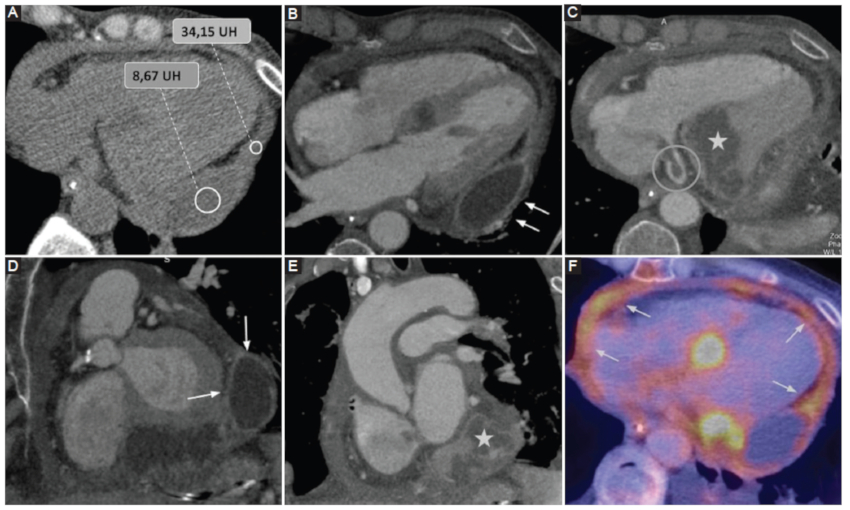

Compromiso del pericardio por patología tumoral

Los tumores del pericardio se clasifican en benignos (lipomas y fibromas) o malignos (mesotelioma, linfoma y sarcoma). Si bien son raros, dentro de ellos el más frecuente es el mesotelioma, con un pronóstico ominoso. Por su parte, las metástasis representan la neoplasia más frecuente del pericardio, siendo los tumores primarios involucrados: pulmón, mama, linfoma y melanoma (Fig. 8) (6.

Los métodos por imágenes revelan la presencia de compromiso pericárdico, así como signos de afectación extrapericárdica (parénquima pulmonar, estructuras mediastinales y óseas). Los hallazgos por TCMC presentan una amplia variabilidad de presentación, entre los que se menciona:

DP, generalmente del tipo exudado.

Engrosamiento irregular del pericardio.

Lesiones nodulares y masas pericárdicas.

Adenomegalias mediastinales (definiéndose como ganglios linfáticos mayores a 10 mm en su eje corto).

En este sentido, resulta mandatoria la correcta diferenciación entre recesos pericárdicos voluminosos y ganglios linfáticos patológicos mediante métodos por imágenes1,6,11.

Puede presentarse DP en cuantía variable como signo de infiltración tumoral directa, aunque hasta en dos tercios de los pacientes se debe a causa no tumoral6,12. Al respecto, Thurber et al. (13, en su estudio de más de 13,000 autopsias, encontraron 189 casos de afectación tumoral del pericardio, siendo el DP el hallazgo más frecuente. Aún más, concluyeron que hasta un 85% presentaba DP de tipo fibroso, lo cual traduce la presencia de un exudado13.

Por último, los métodos por imágenes permiten discriminar entre la presencia de pseudomasas (como una almohadilla epicárdica prominente) de tumoraciones pericárdicas2.

Hemopericardio

Se define como la presencia de contenido hemático en el espacio pericárdico, que puede darse en diversos contextos clínicos:

Iatrogénico: en este grupo se engloban el hemopericardio secundario a procedimientos cardiacos invasivos tales como la intervención coronaria percutánea o la colocación de marcapasos (Fig. 9); o como consecuencia de una cirugía cardiovascular (Fig. 10).

Trauma torácico: fuerzas de alta energía que llevan a la presencia de hemopericardio, ruptura pericárdica, taponamiento cardiaco y/o herniación.

Síndrome aórtico agudo: en este contexto, el hemopericardio ocurre con una frecuencia estimada de entre un 17-45%, hecho que contraindica la pericardiocentesis y representa una emergencia clínica (Fig. 11) (6.

Los métodos por imágenes están indicados para la valoración de cuantía y severidad con un nivel de evidencia B clase 1 según las guías vigentes6. Según la serie de Rifkin et al. (3, la TCMC, entre otras cosas, permite identificar la presencia de hemopericardio ante una densidad promedio mayor a 30 UH con una sensibilidad cercana al 100%.